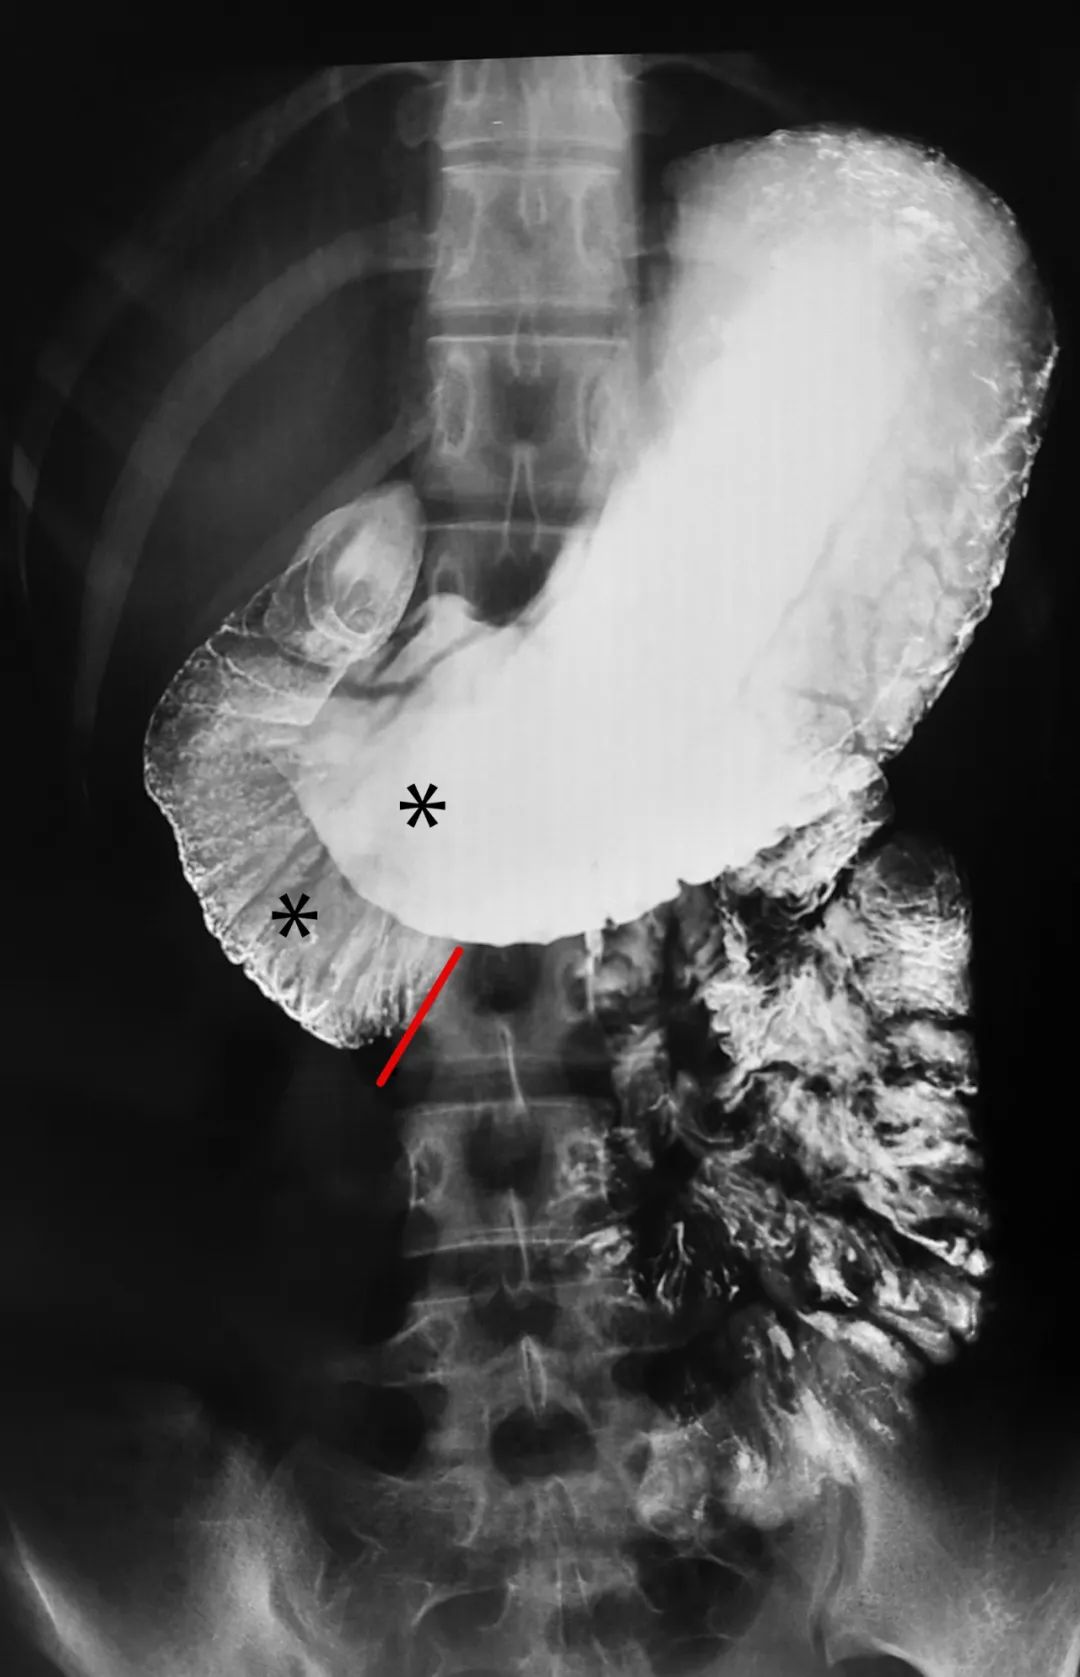

复查胃镜示慢性浅表性胃窦炎,故开放饮食,患者无腹痛、恶心、腹胀等不适,行上消化道造影示“十二指肠淤积可能;胃下垂,轻度胃窦炎”。请外科会诊后,转入胃肠外科。

X 线钡餐常有十二指肠水平部脊柱中线处中断。主动脉和肠系膜上动脉之间的夹角20°。主动脉与肠系膜上动脉之间的距离2.9mm。

●十二指肠梗阻,以空气或钡剂在十二指肠第3部突然中断为特征,并有蠕动活跃的证据。